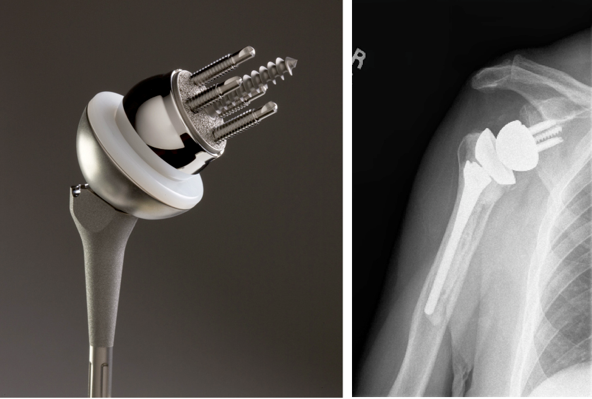

위의 사진과 같이 기존의 인공관절은 humerus 의 골두를 제거하고 glenoid 모습과 비슷하게 작동하는 원리로 인공관절이 되었으나 최근에는 humerus head 의 medialization 효과와 deltoid muscle lever arm의 증가로 더 효과가 있는 reverse shoulder arthroplasty 가 많이 시행되고 있습니다. 1990년대부터 수술을 시작했으니 30년 정도 지난 수술법입니다.

쉽게 생각하면 Convex 와 Concave가 반대로 된 구조라고 생각하면 됩니다. 회전의 중심(Center Of Motion)이 좀더 아래와 안쪽에 위치한 생역학적 장점을 갖고 있습니다.